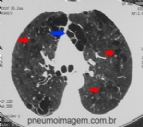

A MAIORIA DOS RADIOLOGISTAS NÃO VIU O GORILA NESTA TOMOGRAFIA

O prof. Trafton Drew, da Harvard Medical School, começou a visitar as "salas de leitura" onde radiologistas fazem seu trabalho. Durante horas ele os observou, no temor de que eles poderiam facilmente ver nas imagens precocemente aquelas coi...